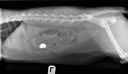

CE estomac chat

Corps étranger 1

22 avril 2012